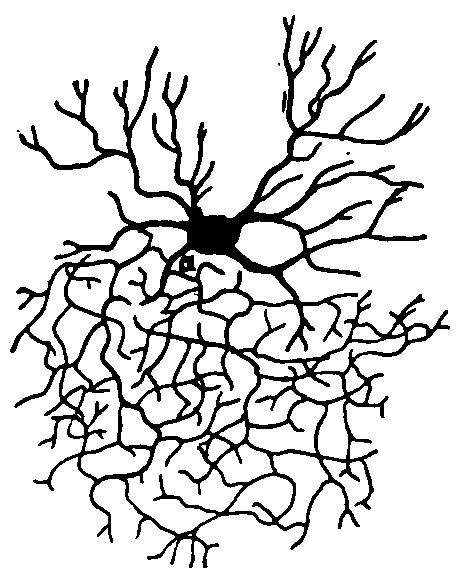

| 16. | Neuroglia cell from the subcortical layer of the cerebrum from which two processes go to a blood vessel | 122 |

| 18. | An artery from the cerebral cortex | 125 |

| 19. | Neuroglia cells of the superficial layers of the brain from an infant aged two months | 126 |

| 20. | Complexity of cell of the central nervous system | 131 |